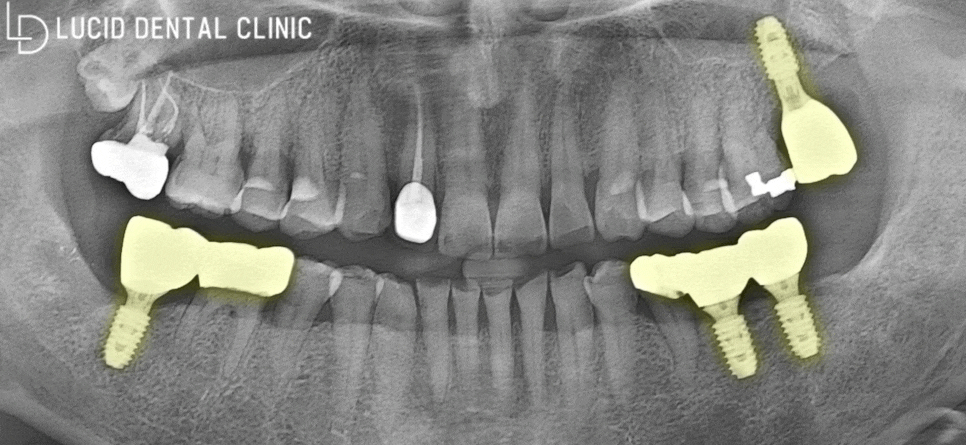

👇 요약 이미지 👇

먼저 임플란트는 위와 같이

자연치와 유사한 모습으로

치조골에 고착되어 있는데요

임플란트 는 보통 위와 같이

3가지의 구조로 이뤄지는데요

crown

abutment

fixture

이 세 가지 구조 중에서

초기 고정력을 판단할 수 있는 요소는

fixture 가 뼈에 고착되는 강도입니다.